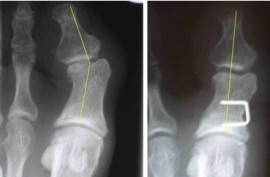

Chevron-Osteotomie:

Diese OP-Methode kommt bei milden bis mittleren Abweichungen der Großzehe zur Fußaußenseite hin zur Anwendung. Der Winkel zwischen dem 1. und 2. Mittefußstrahl (IM-Winkel) sollte einen Winkel von 15° nicht überschreiten. Das Köpfchen des 1. Mittelfußknochens wird hierbei soweit zur Fußaußenseite hin verschoben, bis eine gerade Ausrichtung der Großzehe erzielt wird. Das Korrekturergebnis wird mittels einer Schraube gesichert. Gleichzeitig wird die Kapsel am Großzehengrundgelenk außenseitig gelockert und innenseitig gerafft.